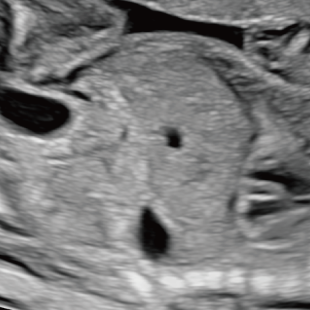

妊娠中期になると、胎児の体や内臓の構造がよりはっきりと確認できるようになります。 中期スクリーニングでは、頭部、顔面、頸部、胸部、腹部、心臓、手足、外性器、臍帯や胎盤など、全身をくまなく観察し、形態の状態を詳しく確認します。この頃に染色体数の変化を疑わせる所見が確認される事もあります。

胎児ドックの様子_中期_頭 胎児ドックの様子_中期_顔面 胎児ドックの様子_中期_心臓 胎児ドックの様子_中期_腹部 胎児ドックの様子_中期_足 胎児ドックの様子_中期_4D